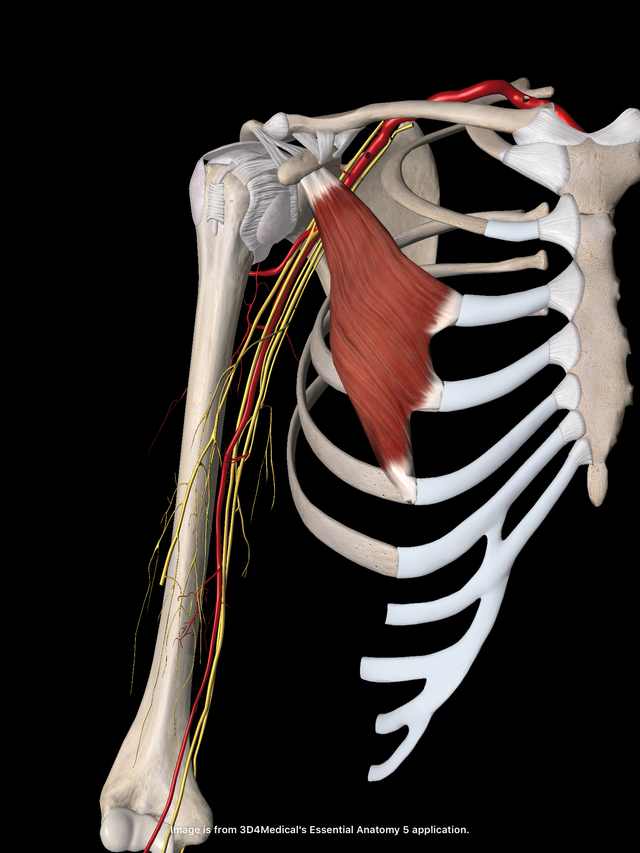

小胸筋と肩甲骨 腕のしびれにも関連

イラストは肩を前から見たところです。

胸の深層には小胸筋という肩甲骨の烏口突起という

隆起部からのびる筋肉が肋骨に付着しています。

この筋肉の緊張は肩甲骨を前傾させ、

肩が前に入った状態に固めてしまいます。

肩が前に入った状態は

非常に肩こりになりやすい状態でもあります。

実は肩こりの根本的な改善は肩のコリを「もみほぐす」のではなく

この小胸筋の緊張をとることによってなされるのです。

また、小胸筋の下には血管や神経が走行していますので、

腕のしびれ・冷えなどの症状がある場合も、

小胸筋の緊張が関係していることがとても多くあります。

この小胸筋は、手を肩の高さで壁について

肩甲骨を後ろに持っていくことで伸ばすことができます。